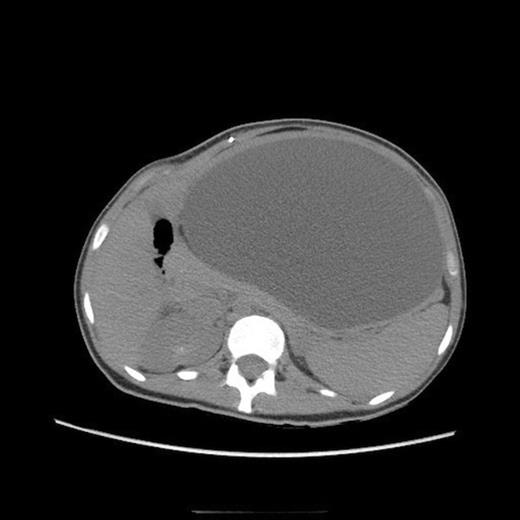

Abdominal CT, axial view, demonstrating a large fluid compartment surrounding the VP shunt catheter resulting in mass-effect, hydronephrosis, and displacement of the intra-abdominal contents

She eventually sought medical attention when she began developing diffuse, unremitting bilateral lower quadrant pain as her abdomen continued to enlarge (Fig. 1). A urine pregnancy test on admission was negative. Abdominal CT demonstrated a large fluid compartment surrounding the VP shunt catheter resulting in mass-effect, hydronephrosis, and displacement of the intra-abdominal contents (Fig. 2 and 3), establishing a diagnosis of APC.